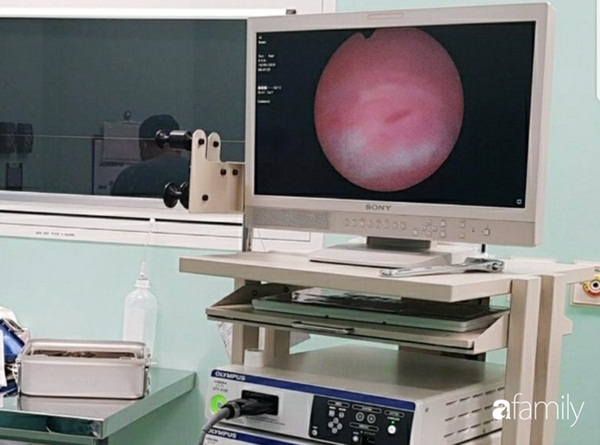

Các bác sĩ khoa Ngoại Niệu và đơn vị Phẫu thuật trong ngày tiến hành nội soi gắp dị vật là cái kẹp tóc bằng kim loại đã rỉ sét do bị quá lâu nên oxy hóa trong âm đạo.

Các bác sĩ cho biết đối trường hợp dị vật âm đạo ở trẻ gái nội soi âm đạo gắp dị vật là biện pháp tốt nhất vì quan sát được rõ bên trong.

Đồng thời, ống nội soi phải là ống nhỏ dành cho trẻ sơ sinh để tránh gây tổn hại và rách các mô mềm xung quanh, nhất là màng trinh của bé.